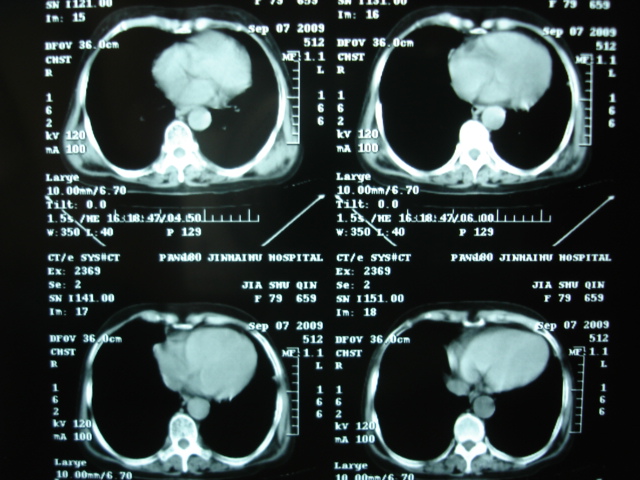

以下是引用卜一在2009-9-7 19:51:00的发言:[br][br] 1 左侧胸内甲状腺占位-多考虑甲状腺腺瘤! 2、左肺门占位-建议增强扫描以便明确性质。 3 慢支并感染! [br]

以下是引用shibing在2009-9-7 20:40:00的发言:[br]左侧胸内甲状腺占位-多考虑甲状腺腺瘤! 2、左肺门占位-建议增强扫描以便明确性质。 3 慢支并感染! [br]